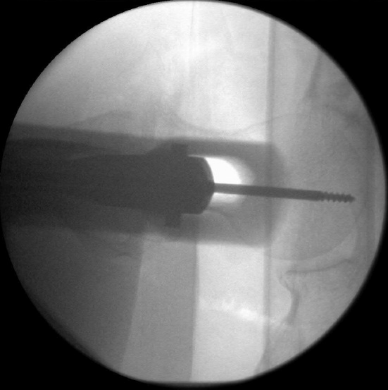

该体位的显著优势在于可清晰观察股骨头颈区域内固定装置的头部组件,这可能是所有体位中对该区域的最佳显像视角(图27与图28)。

什么是c型臂术中透视骨科精读 | 股骨近端骨折的转子区域与矢状面力线术中透视技巧_https://www.jmylbn.com_新闻资讯_第27张

图27

什么是c型臂术中透视骨科精读 | 股骨近端骨折的转子区域与矢状面力线术中透视技巧_https://www.jmylbn.com_新闻资讯_第28张

图28